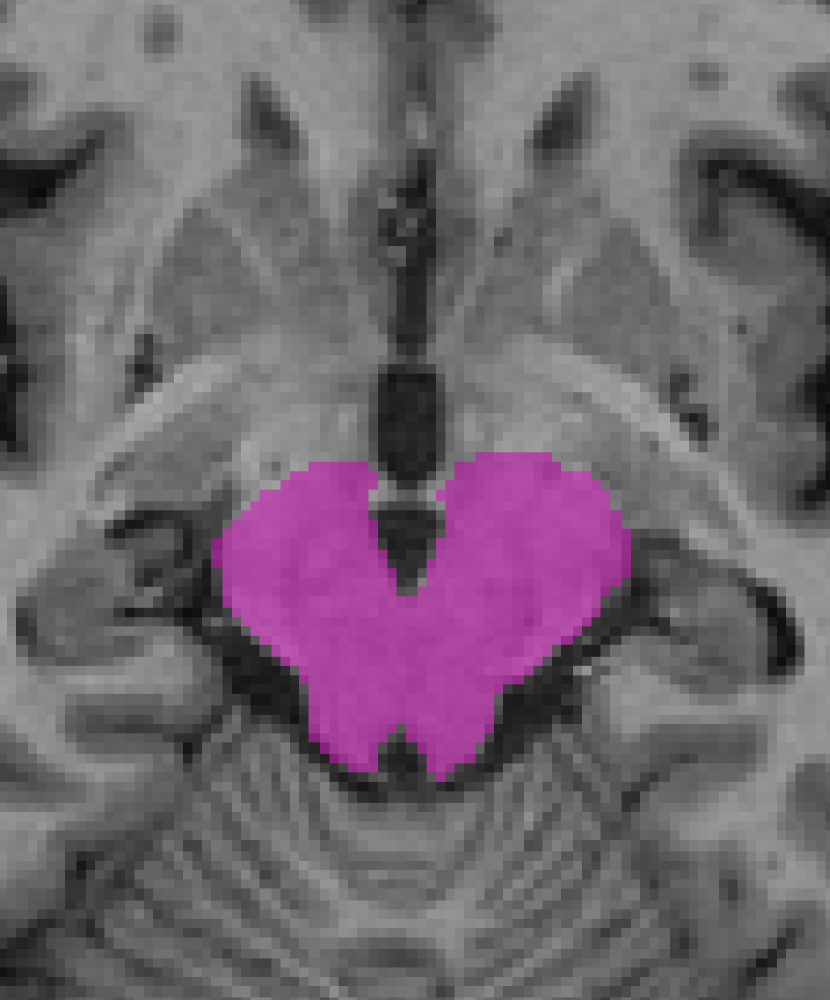

Contrast-driven post-processing techniques may lead to unexpected/unsatisfactory smoothing results. For instance, sub-cortical structures and some parts of the brainstem could be shrunk in this step due to low contrast with surrounding areas as shown in Fig. 7. However, this does not signify that the method is not capable of refining the segmentation since both the intensity features and the prior probabilities take part in the process.

Refer to caption

(a)

(b)

(c)

(d)

Figure 7: Two input slices in which low contrast between the region of interest and the surrounding areas is exhibited. In the image (a) the focus is on the mesencephalon which is highlighted by the purple area in (b). In (c) the focus is on caudate, putamen, pallidum and thalamus structures presented in green in (d).